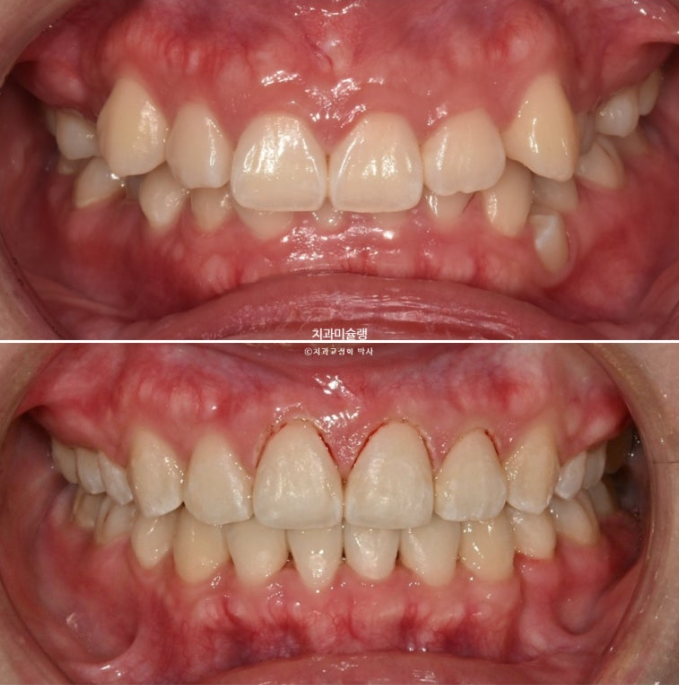

옥니, 덧니, 거미스마일, 중심선 이슈, 약간의 돌출이 함께 있는 상황에서 클리피씨로 거미스마일을 어떻게 해결하는 지 봅시다.

2년 전 교정치료를 위해 온 20대 환자분 입니다.

중심선이 약 2mm 어긋나 있으며 송곳니 덧니가 보입니다.

위 아래 앞니가 깊게 물리는 과개교합도 보입니다.

웃을때 잇몸이 많이 보이는 거미스마일이 있습니다. 특히 위 앞니가 뒤로 쓰러진 옥니 입니다.

25.11

잇몸성형 직후 모습입니다.

앞니 3개에만 시행했습니다.

중심선은 잘 맞고 과개교합도 해소가 되었습니다.

어금니 교합은 물샐틈 없는 1급 교합관계 입니다.

이제 전 후 비교볼게요.

총 치료기간은 2년 3개월 입니다.

깊게 물리는 과개교합이 개선이 되면서 아래 앞니가 비로소 잘 보입니다.

앞니 함입과 잇몸성형의 합작으로 드라마틱하게 개선이 된 잇몸미소 거미스마일 교정

옥니였던 위 앞니 각도가 개선이 되면서 미소가 한층 밝아졌습니다.